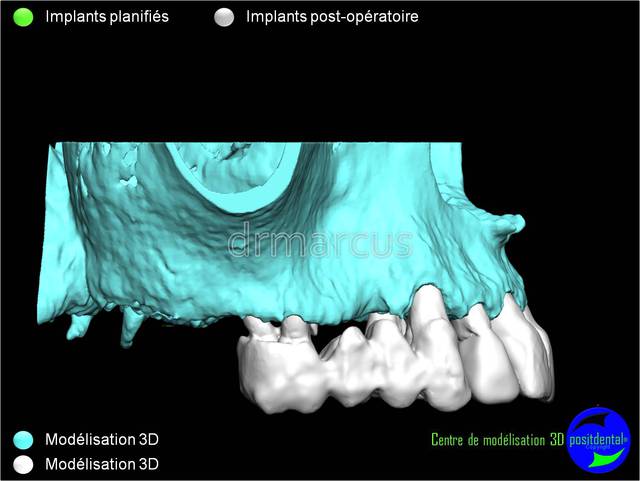

Analyse post-opératoire d’une MCI post-extractionnelle en chirurgie guidée

Cas clinique de drmarcus

Chirurgie : drmarcus

Imagerie 3D: POSITDENTAL

Guide chirurgical : POSITGUIDE

Dispositif de forage : POSITDENTAL

Implant : LEONE

Dommage que ce soit scanner avant et Cone-Beam après. Il est vrai que l’interprétation peut différer. Toutefois on voit la parfaite superposition des implants entre la planification et la réalisation. J'en conclue que le système Positdental est relativement fiable ;-))))